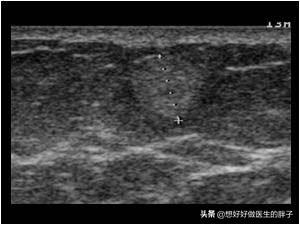

通常医生会给患者做超声的检查,可以简便快捷的明确是否可疑为脂肪瘤。